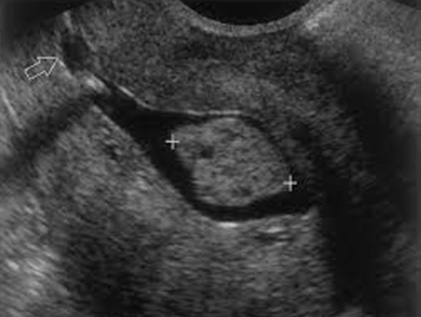

Οι πολύποδες της μήτρας μπορούν να διαπιστωθούν με το διακολπικό γυναικολογικό υπερηχογράφημα αφού η μέθοδος αυτή έχει μεγάλη ευκρίνεια. Σε περιπτώσεις όπου το γυναικολογικό υπερηχογράφημα δείξει ή υποψιαστεί ενδομήτριο πολύποδα, η τελική διάγνωση γίνεται με τρισδιάστηατη υδρουστερουπερηχογραφία (3D SONO) στο ιατρείο χωρίς νάρκωση αφού δεν προκαλεί πόνο,

Εικόνες απο πολύποδες ενδομητρίου με τις δύο παραπάνω μεθόδους.